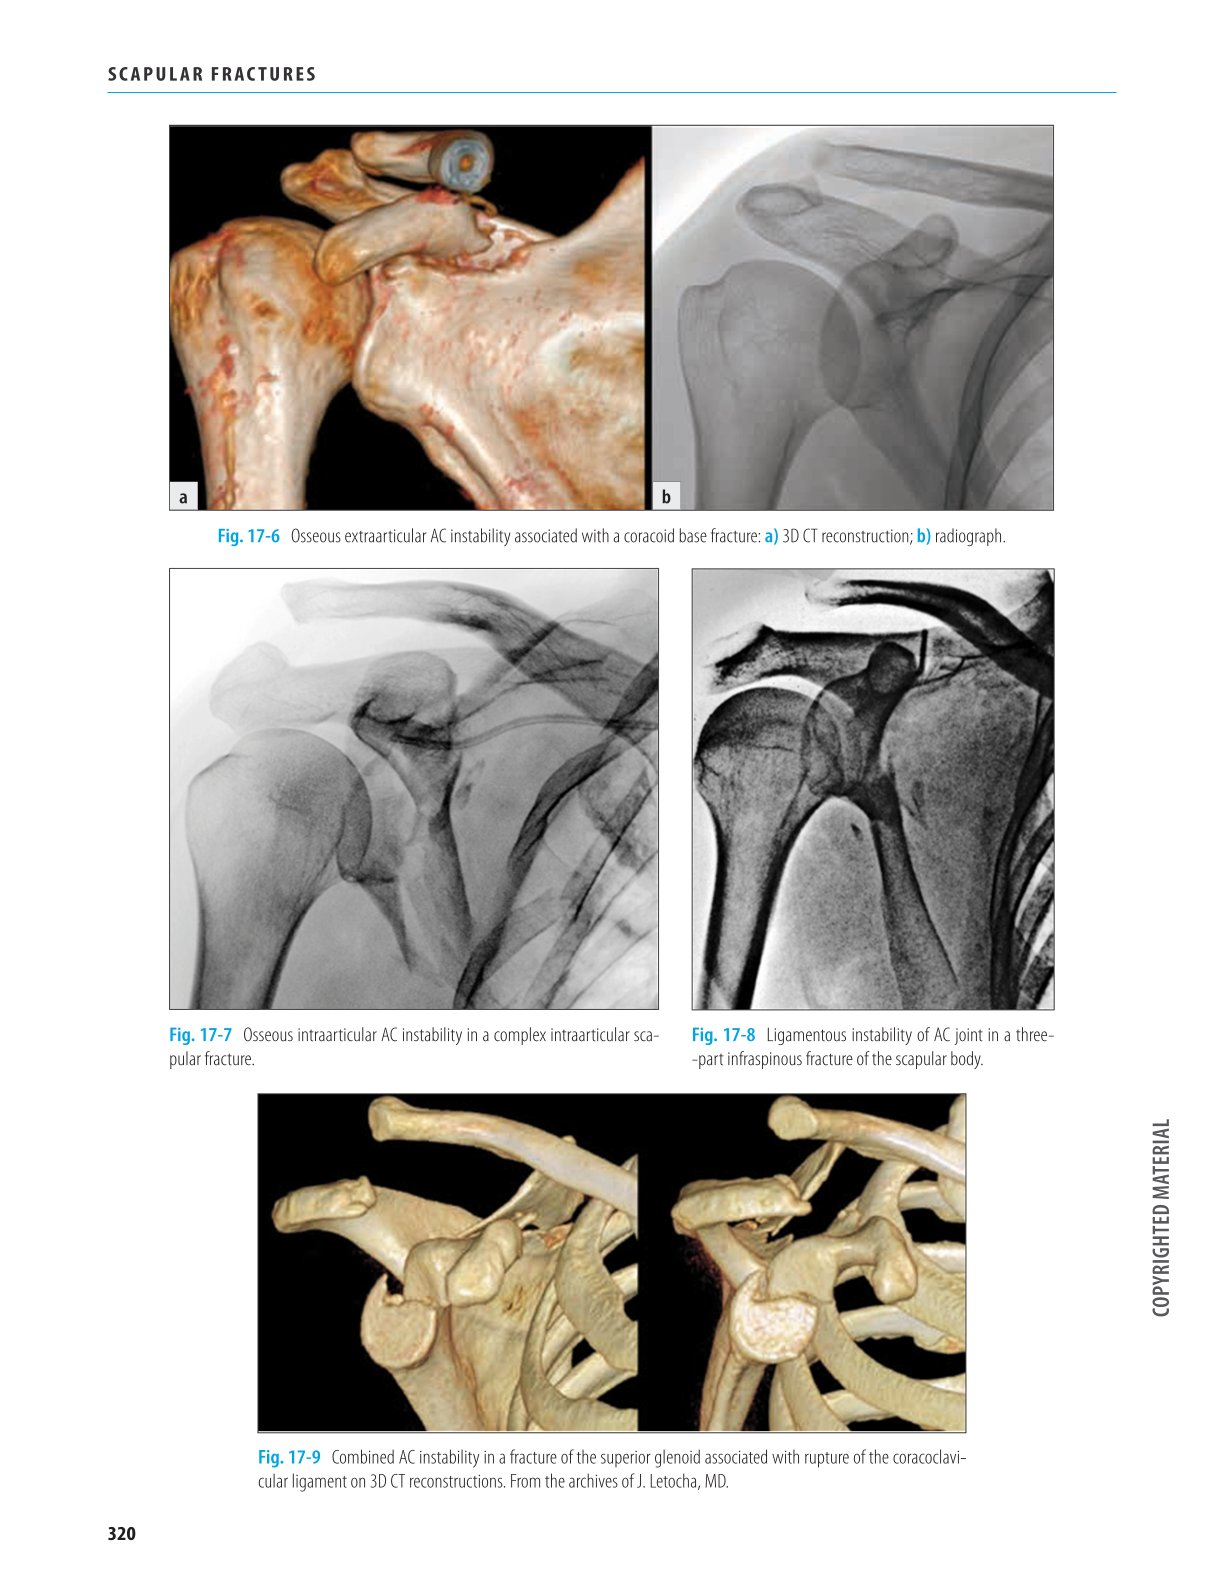

Vznik moderní učebnice by nebyl možný bez nových anatomických poznatků a rozvoje radiodiagnostiky, především CT včetně takzvaných 3D CT rekonstrukcí. Ty umožnily získat dokonalou představu o anatomii zlomeniny. Na jejich základě se lze rozhodnout o způsobu léčby a v případě operace i o nejvhodnějším operačním postupu, což standardní rtg snímky neumožňovaly.